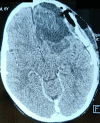

Neuroblastoma represents the most common solid extracranial tumor in children under 5, accounting for 8% to 10% of all childhood cancers. Primary central nervous system (CNS) neuroblastomas are a very rare location and only few cases are available in the literature. It was first described in 1973 by Hart and Earl as supratentorial primitive neuroectodermal tumors. Clinical presentation is highly variable and depends on the initial location of the tumor. Regarding imaging, primary brain neuroblastoma shows no pathognomonic appearance on brain computed tomography (CT) whether or not enhanced or magnetic resonance imaging (MRI). There were no standard guidelines available for the adjuvant treatment in case of primary CNS neuroblastoma. Surgery remains the main and the first tool toward these lesions. Radiotherapy associated or not to chemotherapy is offered based on patient´s age. Here, the authors report a new pediatric case of primitive central nervous system neuroblastoma revealed by an intracranial hypertension syndrome and confirmed by both histopathological and immunohistochemistry study after a gross total surgical excision. The postoperative course was uneventful and the child had good recovery.